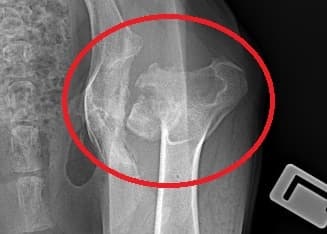

Totální endoprotéza kyčelního kloubu je umělá náhrada kyčelního kloubu zahrnující hlavici femuru (stehenní kosti) a acetabulum (kloubní jamky)

Přesto však Oliver na nohu chodit nezačal. Než pro něj dobrovolníci sehnali nějaké zázemí, byl policii převezen do státního útulku, kde se jeho stav také vůbec neřešil, a celou situaci chtěli vyřešit utrácením. Proto jsme vyhověli prosbě místní organizace a díky první sbírce, kde se vybrala částka dostačující na převoz, jsme Olivera přivezli k nám. Jeho stav byl ve skutečnosti opravdu žalostný, horší než byl na fotkách a videích. Na kost hubený, celý křivý, včetně předních nohou, které díky nerovnoměrné zátěži má celé prošlápnuté. Jeho stav jsme začali okamžitě řešit a Olivera jsme vzali na Animal Clinik v Praze, kde se provedlo kompletní vyšetření a RTG. Rentgenové snímky hovořily jasnou a nesmlouvavou řečí: Oliver měl tříštivou zlomeninu krčku kloubní hlavice a tím i zničenou kloubní jamku. Podle veterináře musel trpět úpornými bolestmi. Byla navržena totální endoprotéza, tedy výměna celé kloubní hlavice a tento zákrok by mu měl pomoci k téměř normálnímu pohybu. Zákrok a vše s ním spojené bude stát cca 100 000,-. Proto vás prosíme o pomoc s jeho léčbou zasláním aspoň malé částky na transparentní účet spolku. Každá korunka se počítá, takže budeme vděčni i za menší obnos. Pomozte nám prosím společnými silami umožnit tomuto úžasnému psímu dobrákovi žít normální život a ukázat mu i tak i tu jeho lepší stránku.